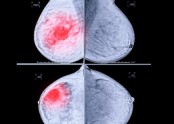

▶ 유방 촬영은 왜 하나요? 등록일 2017-01-26 02:46:55소요시간 : 10분 내외비용 : 1.5만원(보험 적용) - 4.5만원(보험 미적용) ● 유방촬영을 하는 이유는 유방의 패턴을 지방성과 치밀유방으로 분류하고, 암의 소견인 미세 석회화와 혹를 찾기 위해서 입니다.   … |

▶ 양성 석회화가 보인다고 합니다. 무슨 뜻인가요? 등록일 2017-02-26 23:17:43유방에는 아무런 멍우리가 만져지지 않아도 단지 정기 검진 목적으로 시행한 유방 사진 촬영에서는 석회화가 보이는 경우가 자주 있습니다. "석회화"(calcification)"란 유방 사진 촬영에서 유방조직 내에 조개 껍질 같은 칼슘 성분으로 된 미세한 석회질이… |

▶ 정기 검진중 미세 석회화가 발견되었다고 합니다. 등록일 2017-02-26 23:25:02■ 정기적으로 유방촬영하는 것이 왜 중요할까요?    ① 아래 환자분은 30대 중반에 검진상 양성 석회화가 있던 분으로 5년 되던 40세에 국가암 검진을 했고, 이때 과거에는 보이지 않던 소견으로 유방촬영 하부 작은 부위에 … |

치밀유방, 비대칭유방, 국소증가음영, 유방미세석회, 유방촬영 등록일 2025-10-29 11:51:44유방촬영 결과가 ‘치밀유방', '비대칭유방', '국소음영이상'으로 병변 소견이 나오는 경우가 있습니다.유방촬영에서 ‘치밀유방’이라는 판정이 나오는 경우가 많은데 이 때는 유방 내에 종양이 있어도 알 수 없는 경우가 많아서 되도록이면 유방 초음파 검사를 꼭 해보는 것이… |